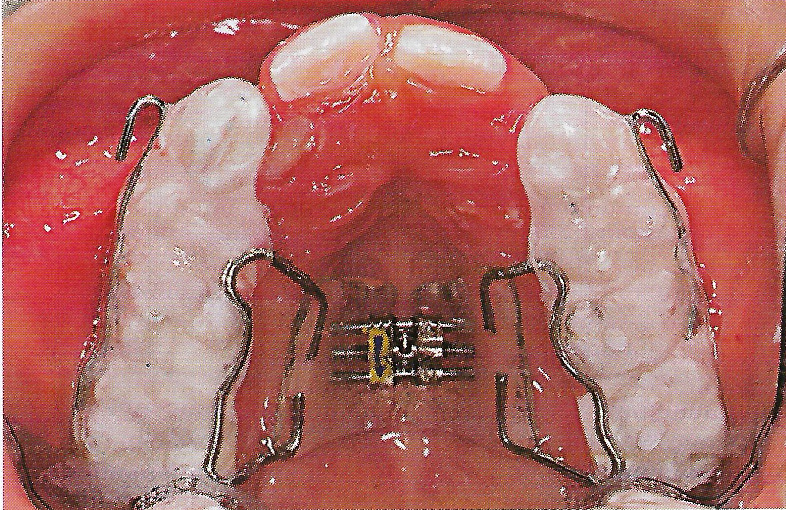

• Ankylose Abb.10

Abb. 10 Mit Glasionomerzement befestigte Dehnungsapparatur mit seitlichen Aufbissen und Frontalzughaken zur Gaumennahterweiterung und Protraktion.

• Eine Gaumennahterweiterungsapparatur in Form einer Kappenschiene wurde zementiert und zweimal täglich aktiviert (Abb. 10). 9 Wochen nach der Replantation wurde ein Frontalzug-Headgear nach Hickham8 eingesetzt, der über Gummizüge zu den Häkchen der Kappenschiene eine Kraft von etwa 4 N (400 g) pro Seite in leicht kaudaler Richtung ausübte (Abb. 11). Der Headgear wurde durchschnittlich 10 Stunden täglich für 8 ½ Monate getragen.